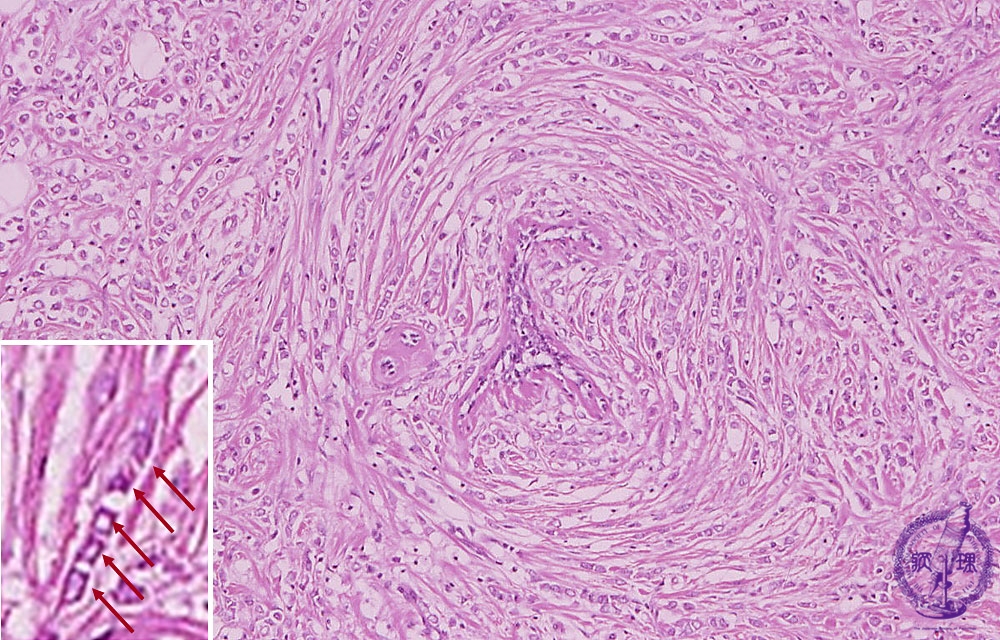

Microscopic image(HE stain, high power view):Stromal invasion of lobular carcinoma. Relatively small carcinoma cells with high N/C ratio infiltrated to the stromain a so-called “Indian-file”manner(inset, arrow).This finding is characteristic of invasive lobular carcinoma.